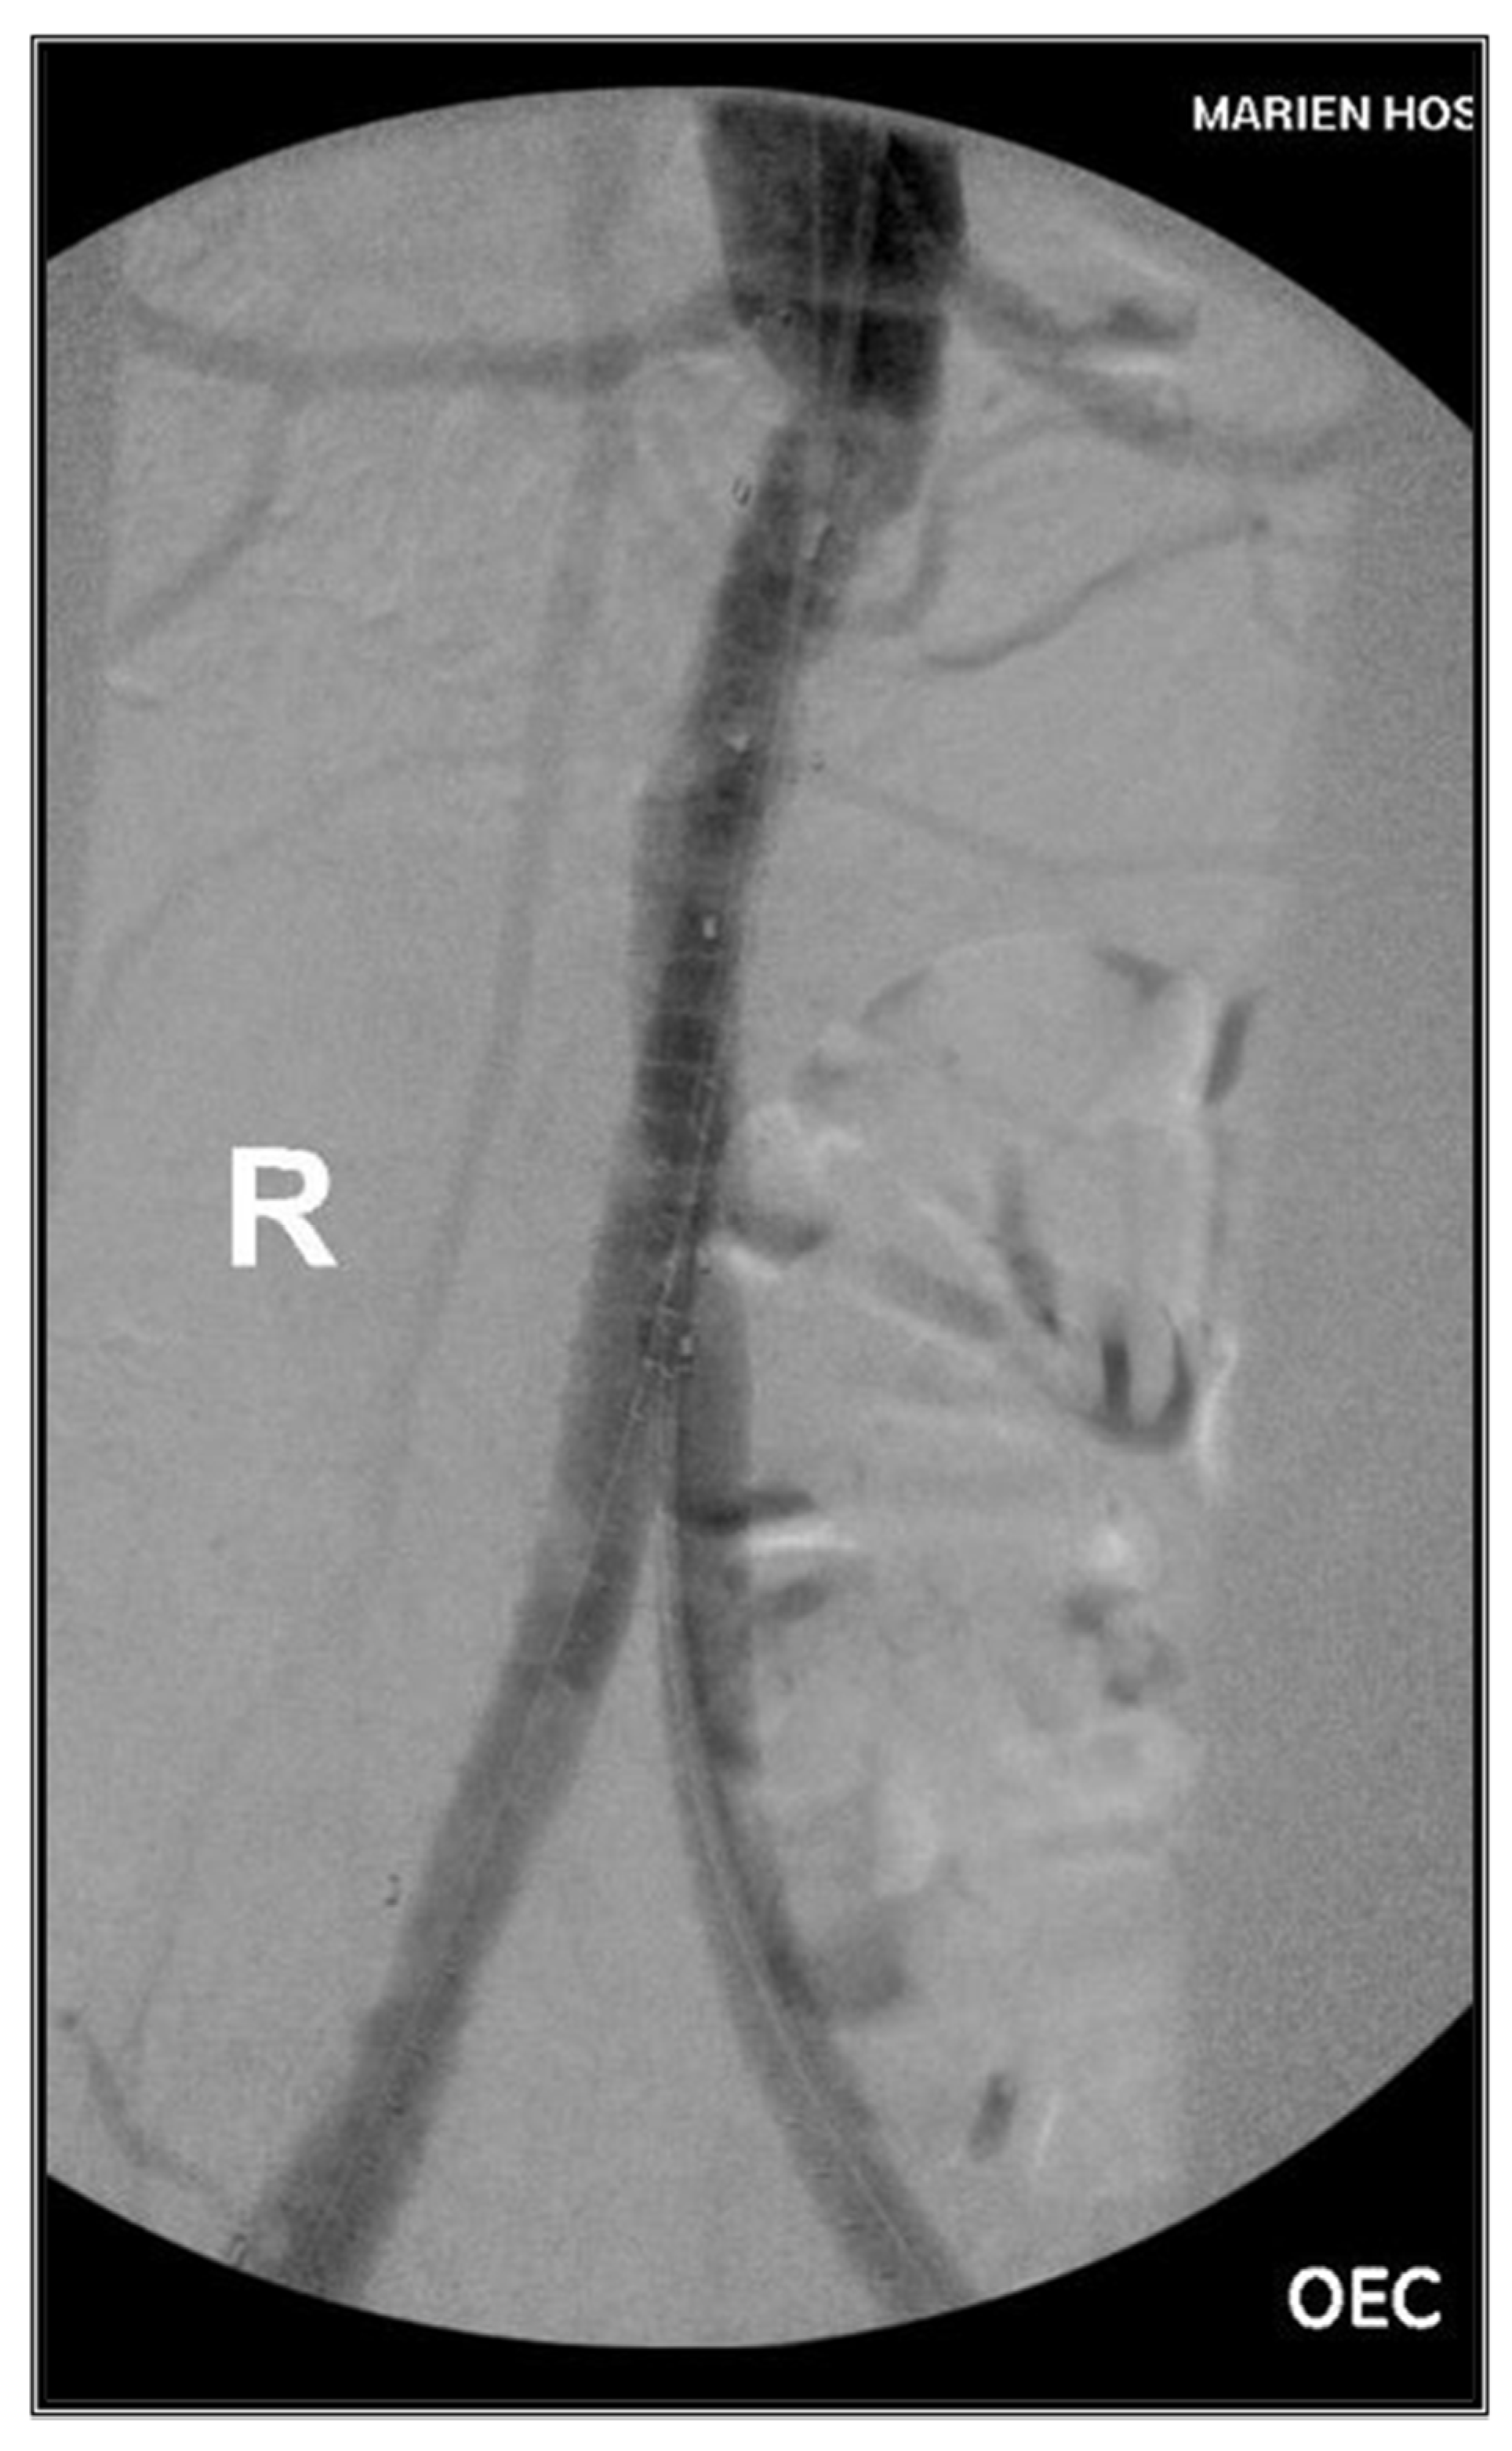

2. Case Presentations

2.2. Case II

3.2. Case II